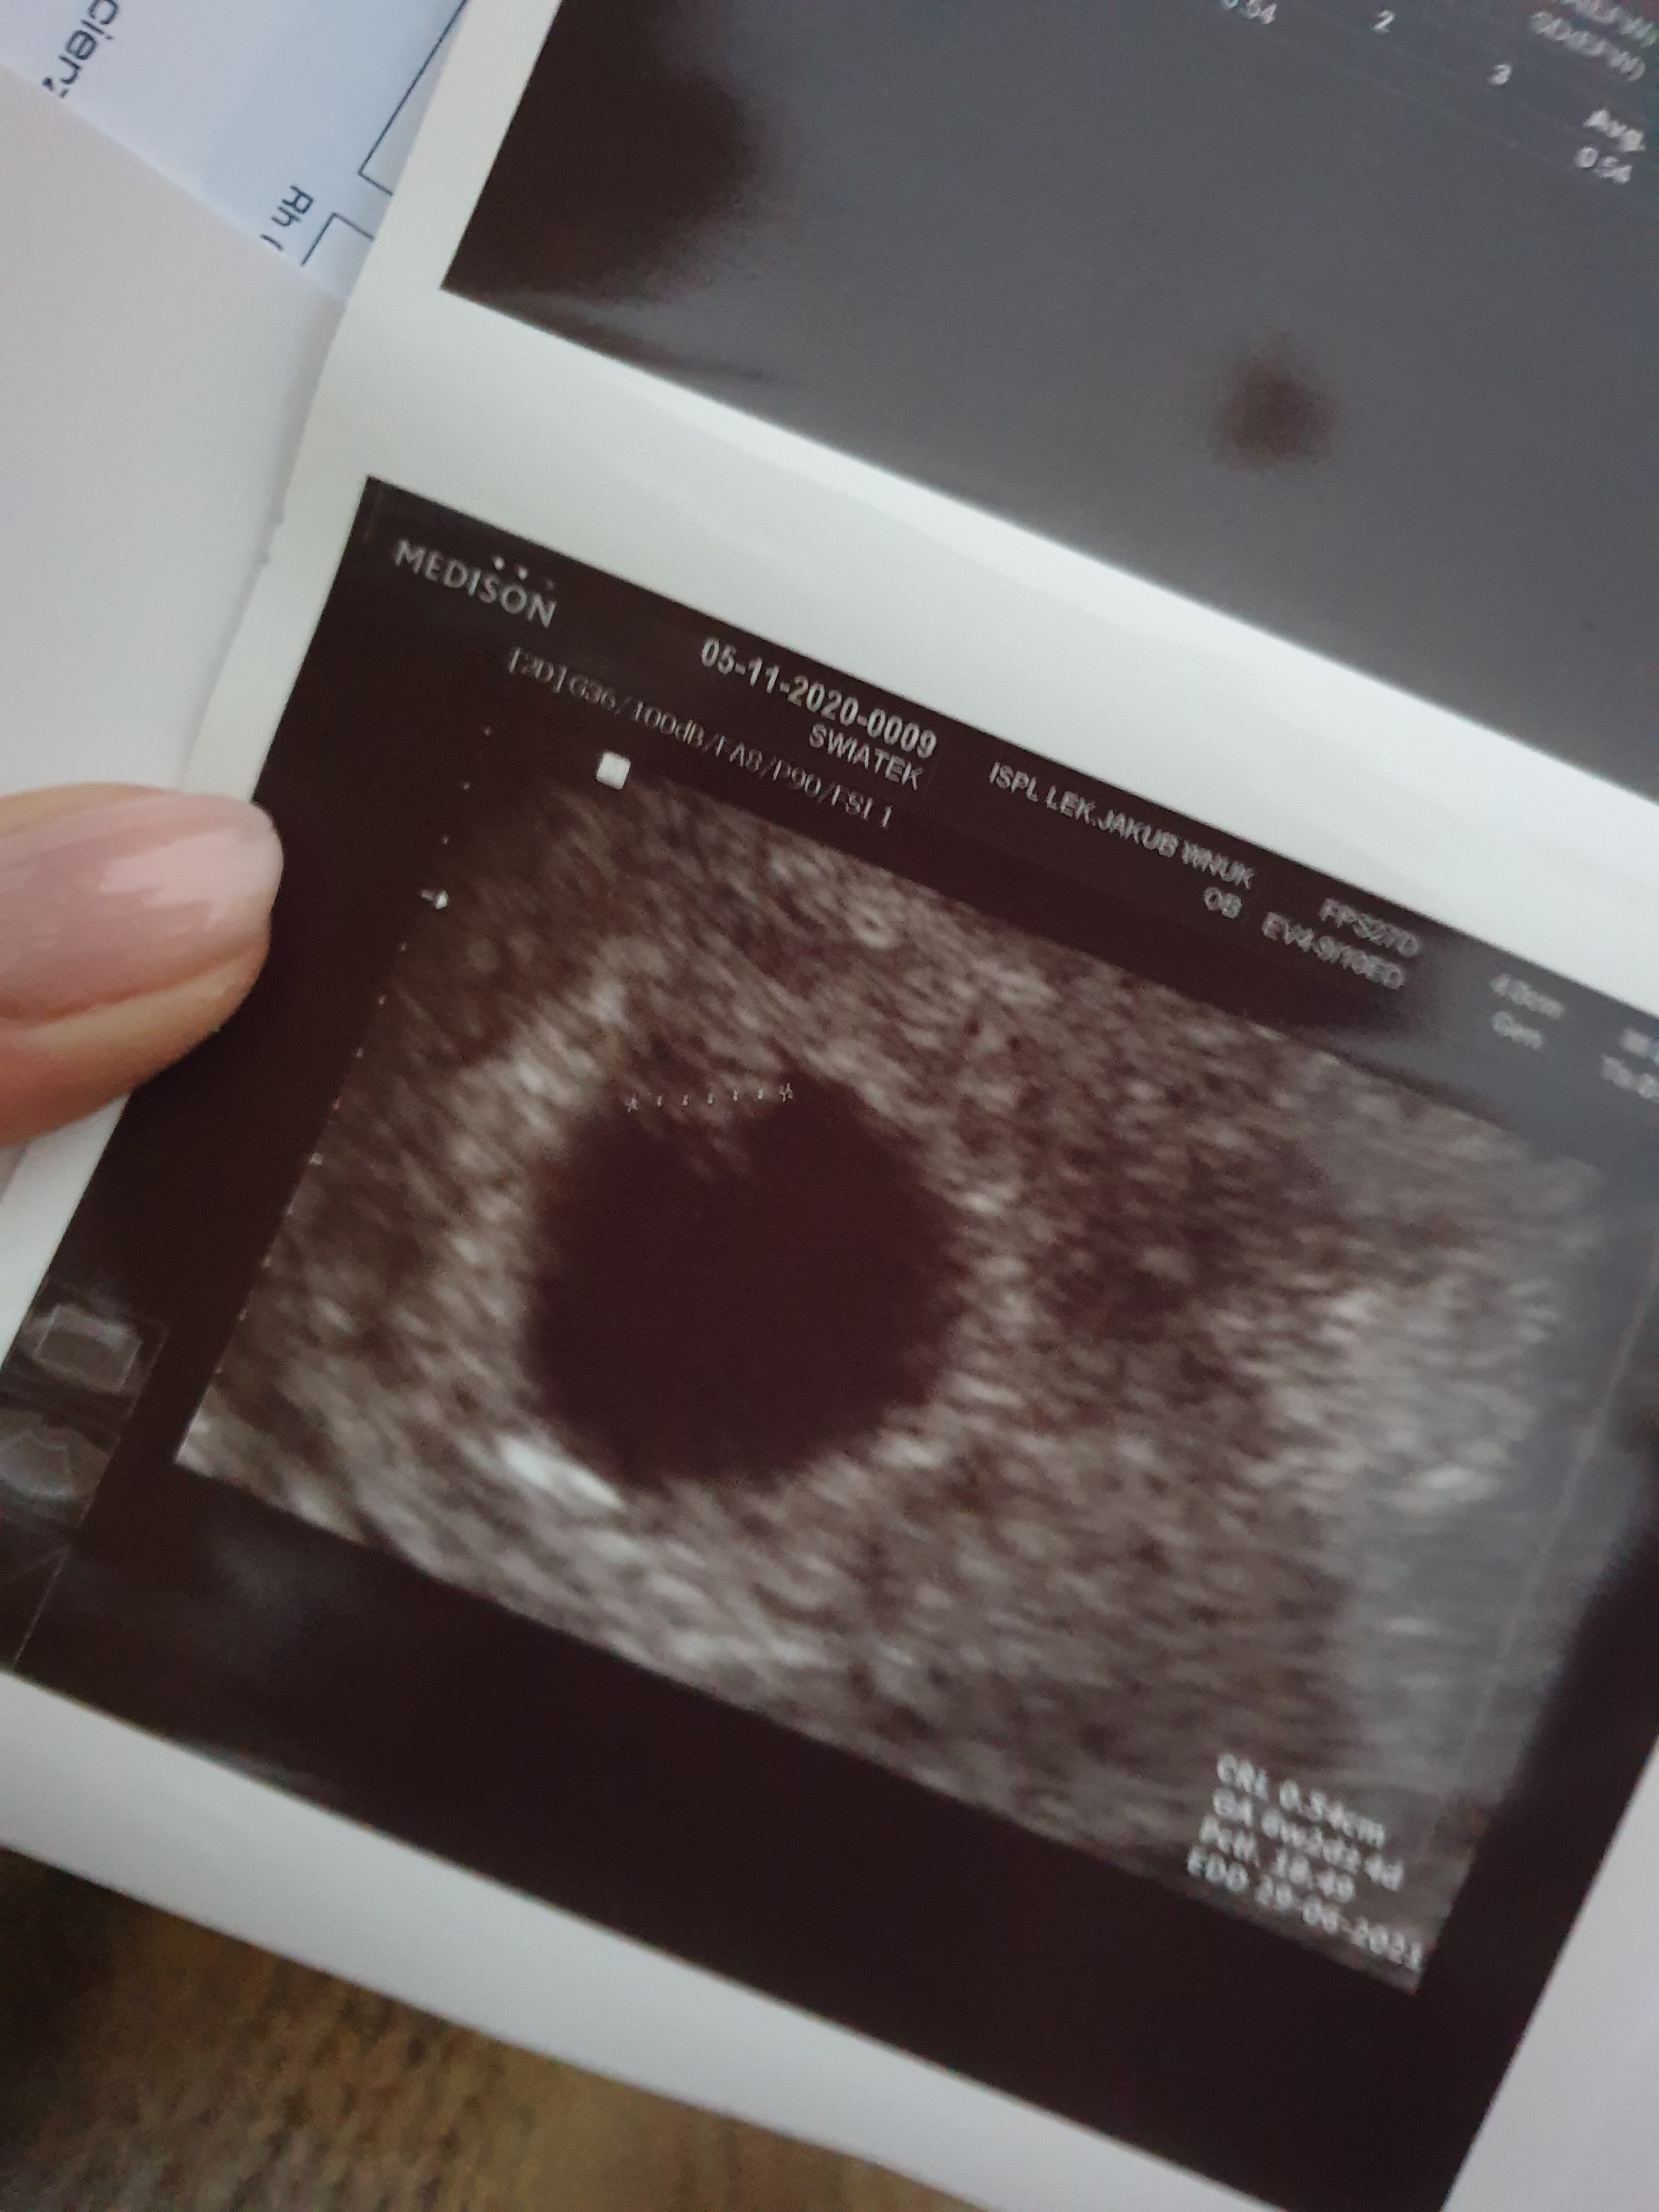

Jest i Junior 😍 6t2d 😍 serduszka nie słyszałam ale widziałam, że pieknie bije.

Ze względu na poronienie 2 lata temu, dostalam duphaston.

Ale jestem szczesliwa ❤ 0.54cm szczescia

Załączniki

• 20201105_162438.jpg

20201105_162438.jpg

1,2 MB · Wyświetleń: 129